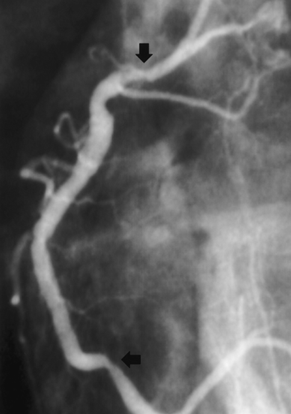

Evaluare coronarografică

- Abord femural drept;

- Sistem coronarian dominant drept;

- Injectarea substanței de contrast în CS – TCS indemn, ADA, ACX fără leziuni semnificative angiografic;

Injectarea în CD – deficit de umplere la nivelul segmentului mediu, fără limitarea fluxului, posibil tromb sau disecție spontană (necesită IVUS sau OCT);

- Concluzie: Artere coronare epicardice fără leziuni semnificative angiografic

- Evaluarea coronarografică a evidențiat deficit de umplere la nivelul segmentului mediu al ACD, fără limitarea fluxului, posibil tromb sau disecție spontană, fără alte leziuni semnificative angiografic.